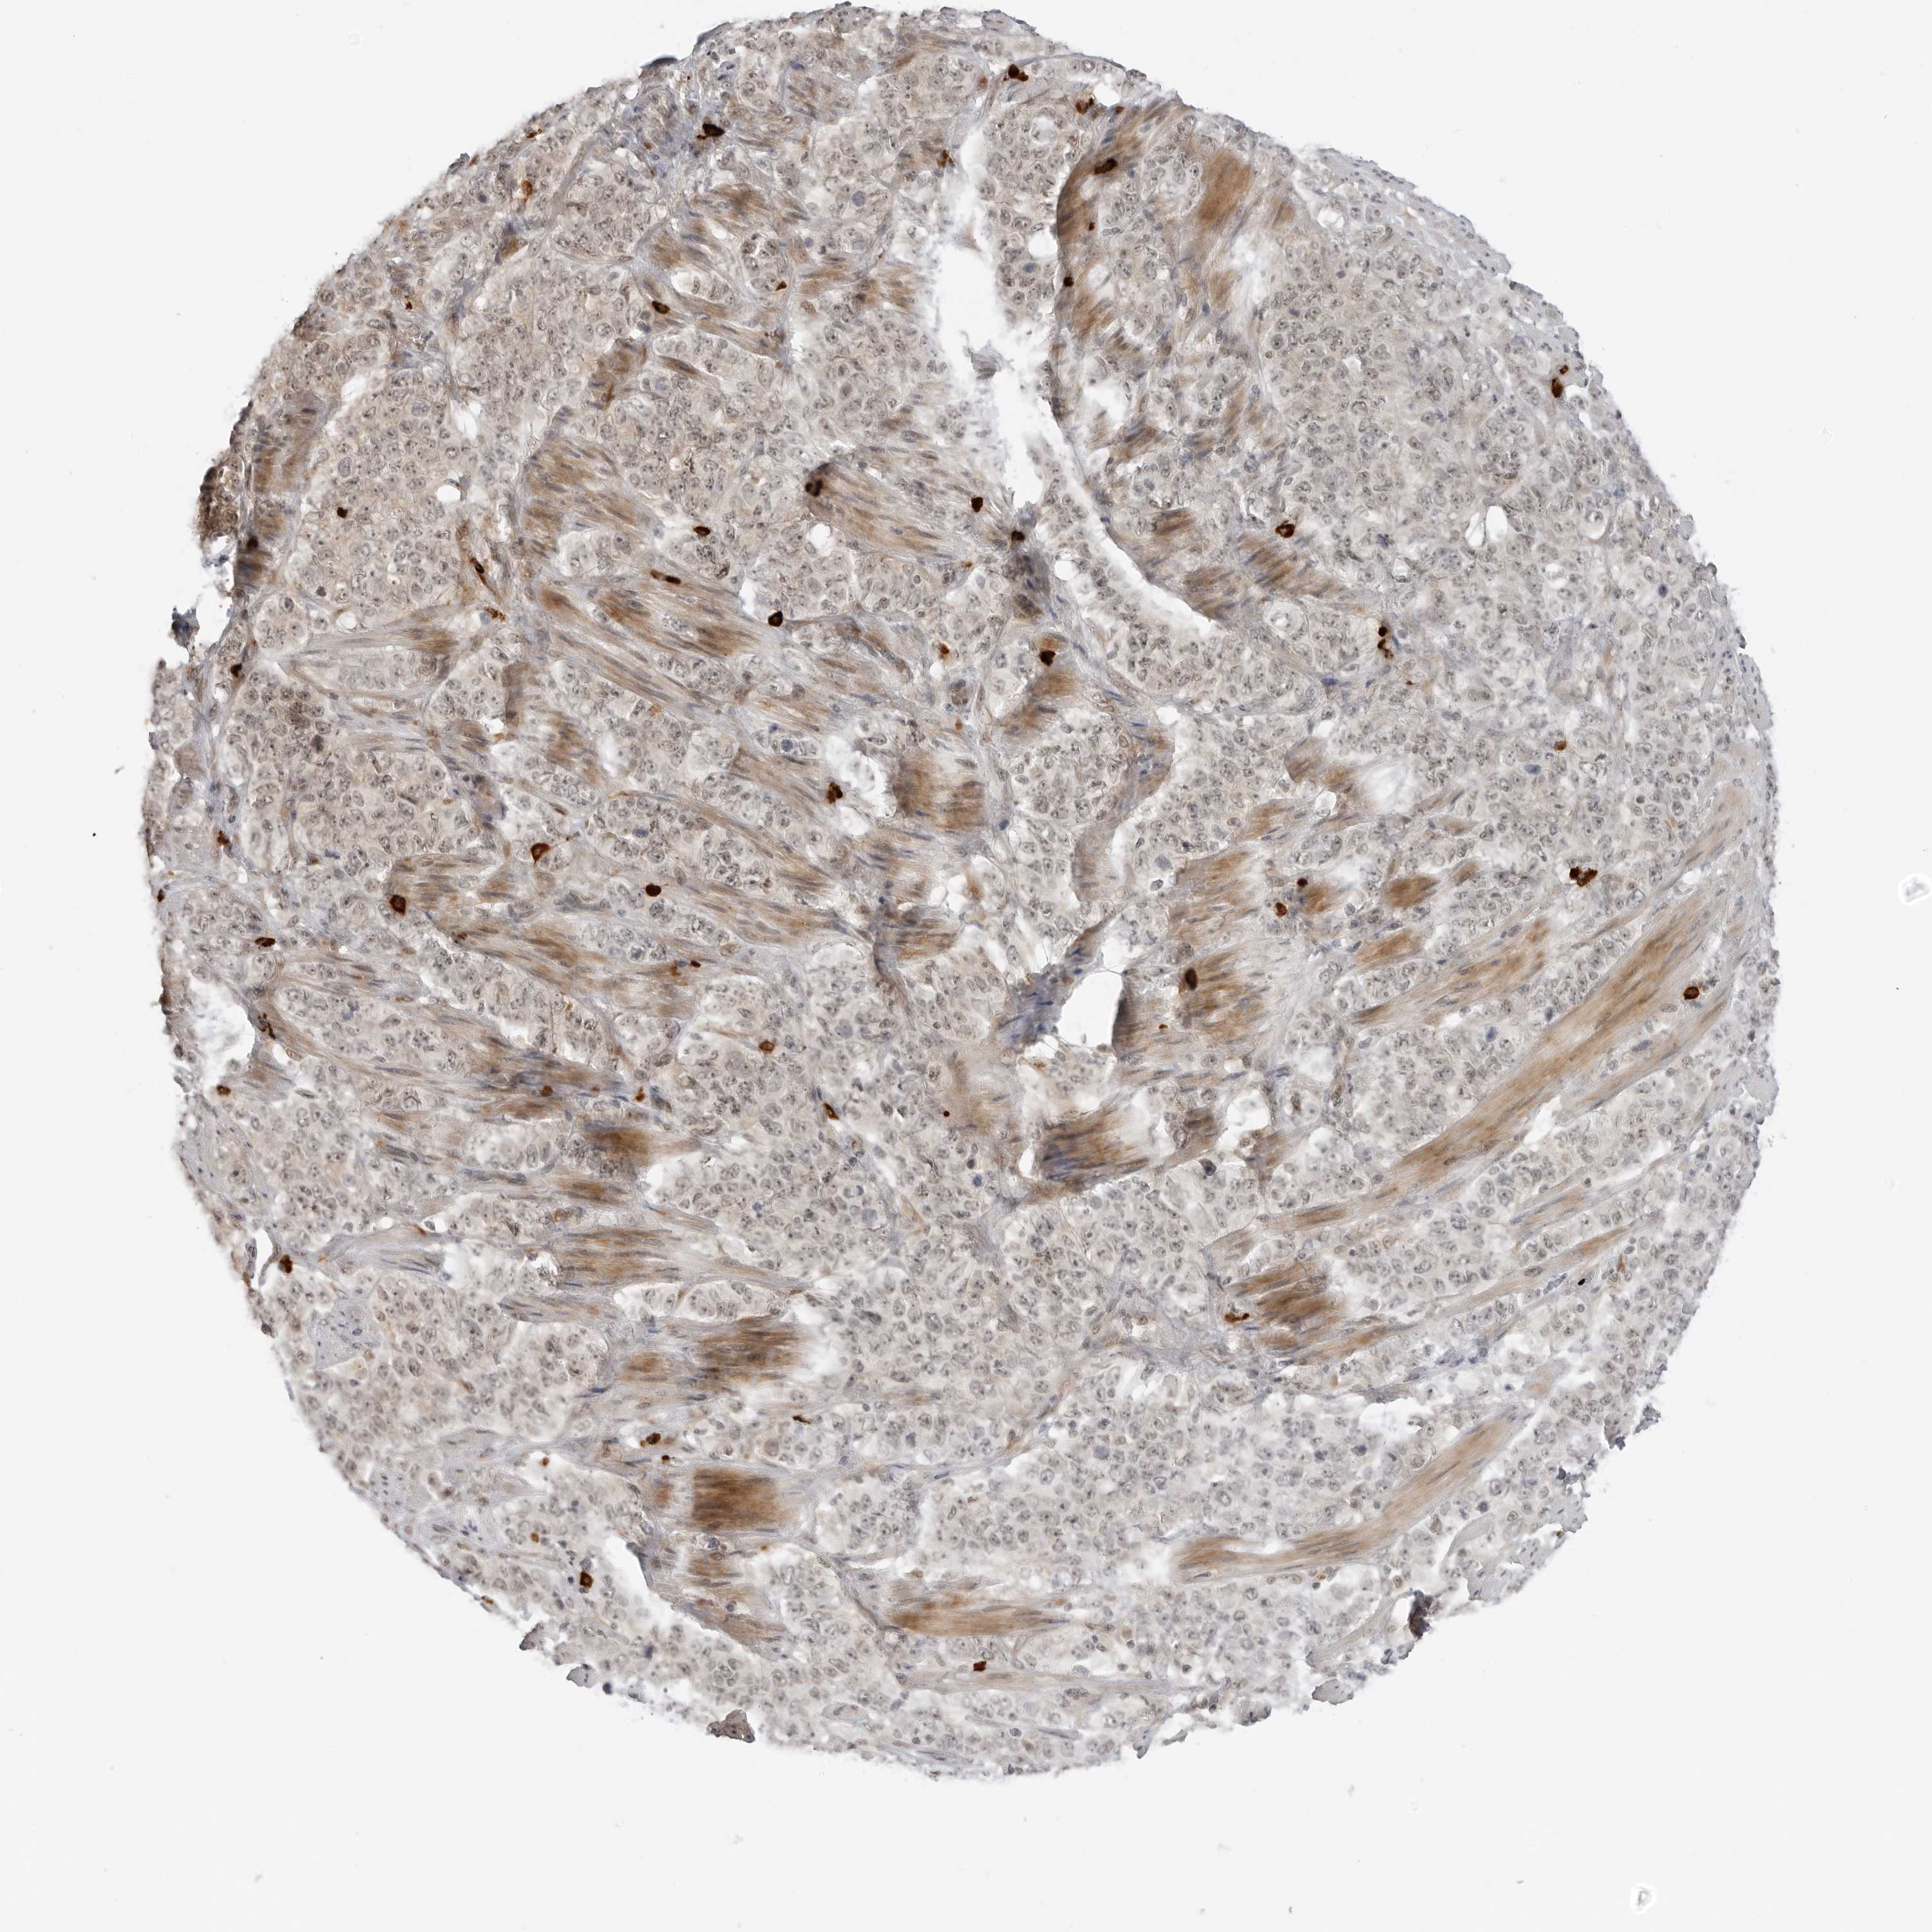

STOMACH CANCER - Protein expressioni

A mouse-over function shows sample information and annotation data. Click on an image to view it in a full screen mode. Samples can be filtered based on level of antibody staining by selecting one or several of the following categories: high, medium, low and not detected. The assay and annotation is described here.

Note that samples used for immunohistochemistry by the Human Protein Atlas do not correspond to samples in the TCGA dataset.

Antibody stainingi

Antibody staining in the annotated cell types in the current human tissue is reported as not detected, low, medium, or high, based on conventional immunohistochemistry profiling in selected tissues. This score is based on the combination of the staining intensity and fraction of stained cells.

Each image is clickable and will lead to virtual microscopy that enables deeper exploration of all samples and also displays staining intensity scores, fraction scores and subcellular localization as well as patient and tissue information for each sample.

Antibody HPA026698

Antibody HPA026704

Antibody HPA026705

Staining

High

Medium

Low

Not detected

Intensity

Strong

Moderate

Weak

Negative

Quantity

>75%

75%-25%

<25%

None

Location

Nuclear

Cytoplasmic/membranous

Cytoplasmic/membranous,nuclear

Adenocarcinoma, NOS